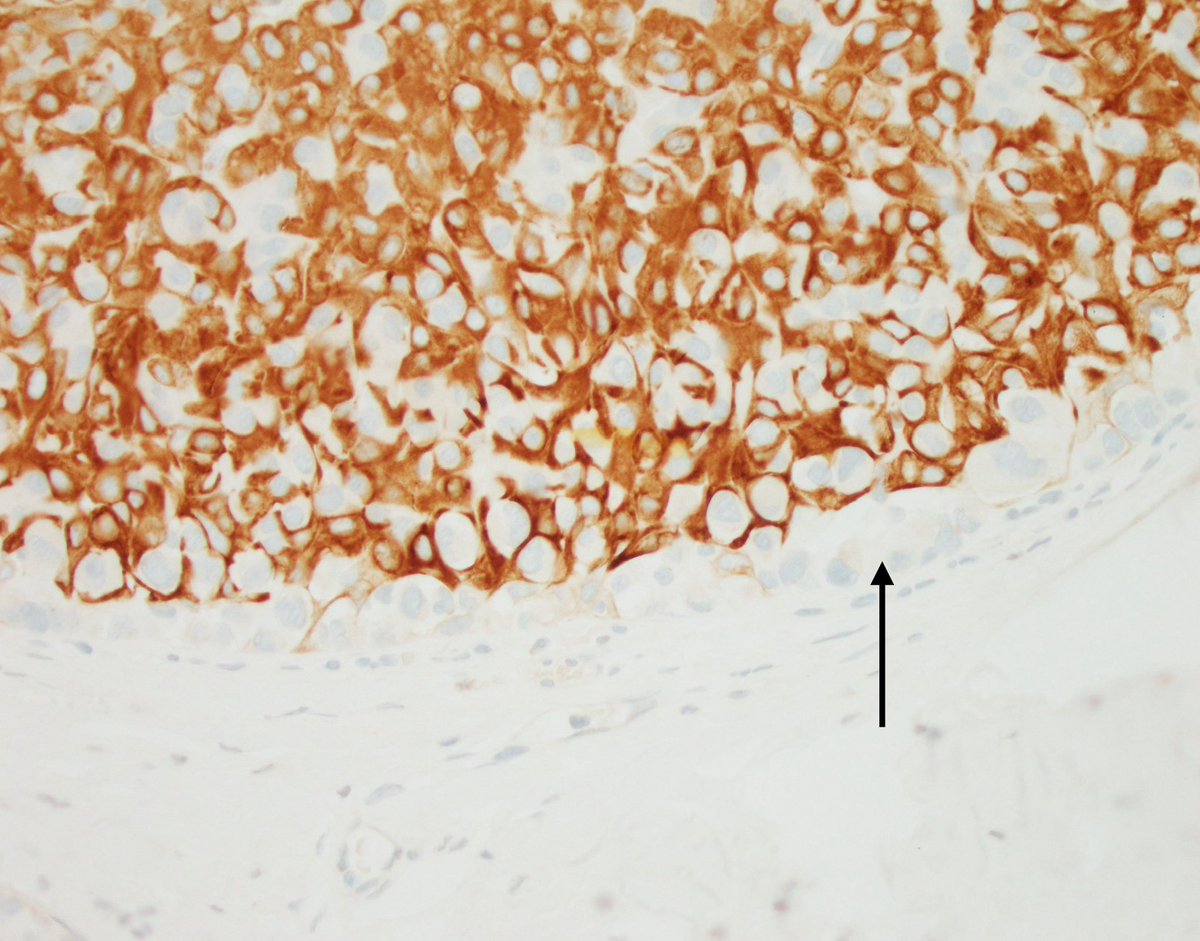

๐ซ Lobectomy. ๐ฌ Lung Adenocarcinoma. ๐ Signet ring cells. โ TTF1. #LungPath #LungCancer #PathX